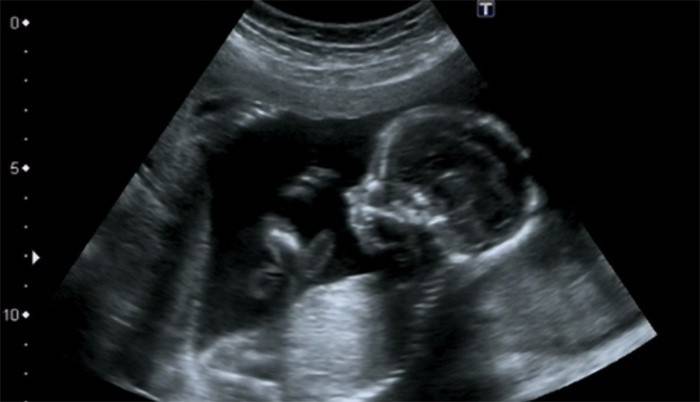

Ultrasonido a las 16 semanas.

Uno de los eventos más emocionantes para los futuros padres cada vez es una ecografía. Ayuda a ver al bebé, distinguir las partes del cuerpo y la cara, movimientos, movimientos y reacciones a estímulos externos. El niño ya puede expresar descontento o alegría con expresiones faciales. Determinan el sexo, también es posible distinguir al bebé durante la ecografía 3D. El médico mide el ultrasonido con ciertos indicadores: altura y peso, la cantidad de líquido amniótico, la circunferencia de la cabeza y el pecho, la longitud de los huesos. Esto da una idea del desarrollo y el momento adecuado. El médico examina cuidadosamente la estructura de la placenta y el lugar de su unión, las paredes del útero y el área de su cuello, el flujo sanguíneo en el cordón umbilical.